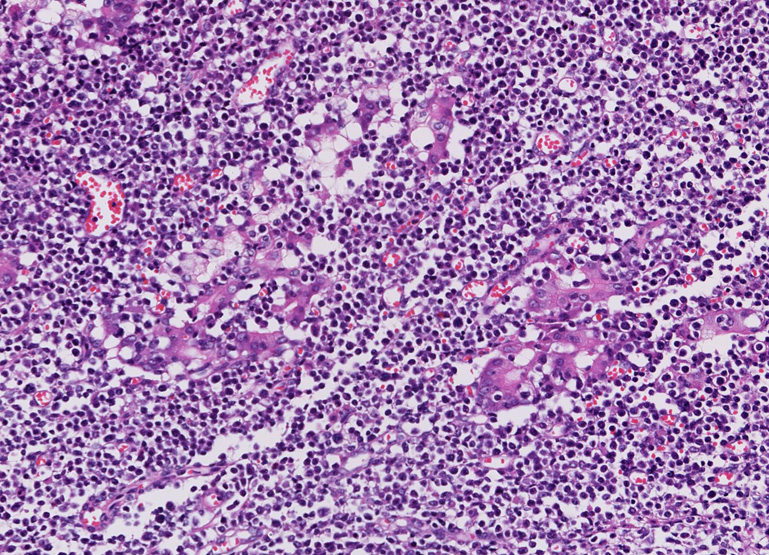

- 典型例はmarginal zoneのcentrocyte-like cellの増殖といわれるが非典型例も多い

- 分化してplasma cell様の形態をとる. Dutcher body(核内偽封入体)など異型所見あり。

| centrocyte-like cell | monocytoid cell | plasmacytoid |

- 豊かな蒼白(pale)の細胞質をもつ小型から中型細胞で核と細胞質が表面上末梢単球に類似している。

核は中心性で丸い. わずかに不整がある. 中等度に凝集したクロマチンをもち核小体はめだたない.*1